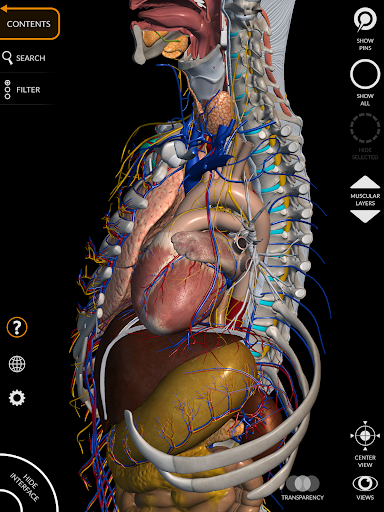

"Anatomy 3D Atlas" vous permet d'étudier l'anatomie humaine de manière simple et interactive.

Grâce à une interface simple et intuitive, il est possible d'observer chaque structure anatomique sous n'importe quel angle.

Les modèles anatomiques 3D sont particulièrement détaillés et avec des textures jusqu'à une résolution de 4k.

La subdivision par régions et les vues prédéfinies facilitent l'observation et l'étude de parties individuelles ou de groupes de systèmes et les relations entre différents organes.

• Système musculo-squelettique

• Système cardiovasculaire

• Système nerveux

• Système digestif

• Faites pivoter et zoomez chaque modèle dans l'espace 3D

• Option pour masquer ou isoler un ou plusieurs modèles sélectionnés

• Filtrez pour masquer ou afficher chaque système

• Visualisation des muscles à travers des niveaux de couches depuis les plus superficielles jusqu'aux plus profondes